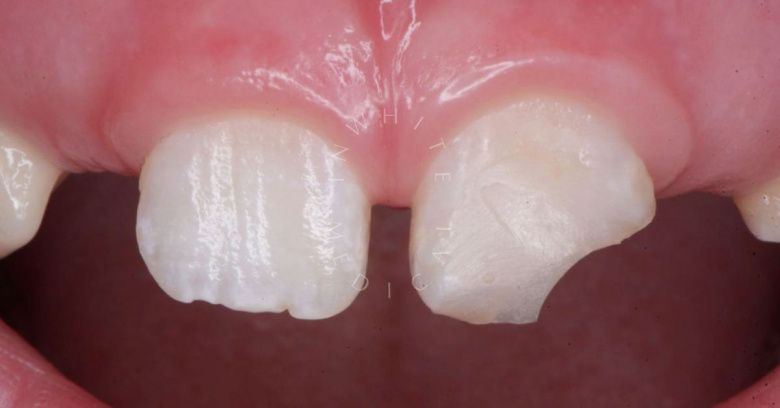

Лечение фиссурного кариеса под увеличением

Стоматология Москва лучшие клиники. Лечение фиссурного кариеса под увеличением - до процедуры